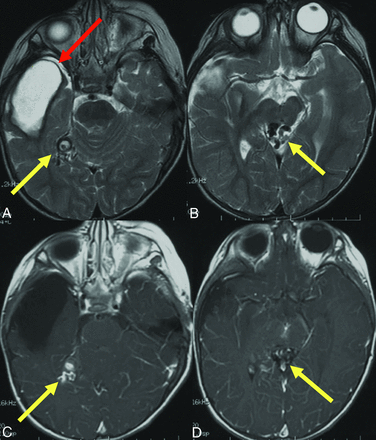

Prior brain hemorrhage in an infant with HHT. T2-weighted MR imaging (A) demonstrates a hemosiderin-lined cavity (red arrow) in the right temporal lobe of a 15-month-old girl with HHT. Additional AVFs (yellow arrows) are evident on T2 (A and B) and contrast-enhanced T1-weighted images (C and D).